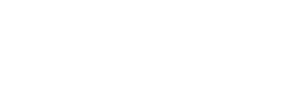

What is Diabetic Retinopathy?

Diabetic retinopathy is a diabetes-related eye condition that affects the retina, the light sensitive layer at the back of the eye, that plays a vital role in vision. It develops when prolonged high blood sugar levels damage the small blood vessels that supply oxygen and nutrients to the retina.

In the early stages, vision may remain unaffected. However, without proper monitoring and management, the condition can worsen over time and lead to vision impairment and in severe cases permanent vision loss.

Diabetic retinopathy develops over time and is classified into two main stages. Each stage reflects the severity of blood vessel damage within the retina.

- Non-Proliferative Diabetic Retinopathy (NPDR)

This is the earlier stage of the condition where small blood vessels in the retina weaken or leak small amounts of fluid, but many patients do not experience noticeable vision changes as symptoms are often absent at this stage. Regular eye examinations play an important role in early detection and allows timely intervention to prevent further progression. - Proliferative Diabetic Retinopathy (PDR)

This is a more advanced stage of the disease. When blood supply to the retina is reduced, the eye responds by growing new abnormal blood vessels. These vessels are fragile and bleed more easily, increasing the risk of more severe vision problems such as vitreous haemorrhage, membranes and traction on the retina, retinal detachment, or even high eye pressures.

- Diabetic Macular Oedema (DMO)

When leakage occurs from the retinal blood vessels located in the central part of the retina, i.e. the macula, fluid accumulates amongst the important light-sensing cells responsible for fine and precise vision. This causes vision to become blurry or distorted.